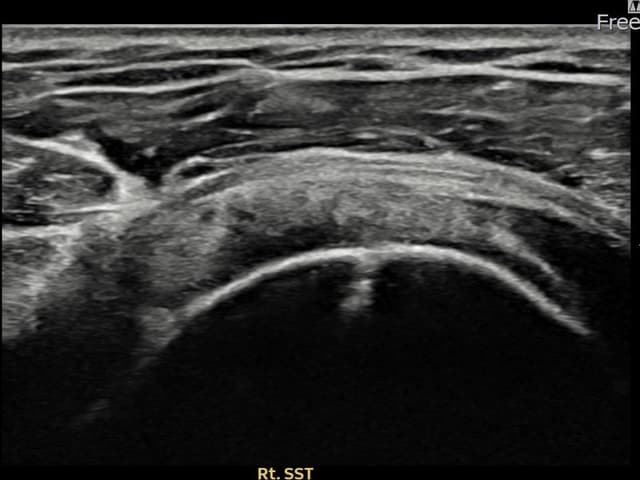

右侧 冈上肌腱 石灰化肌腱炎

14mm × 10mm